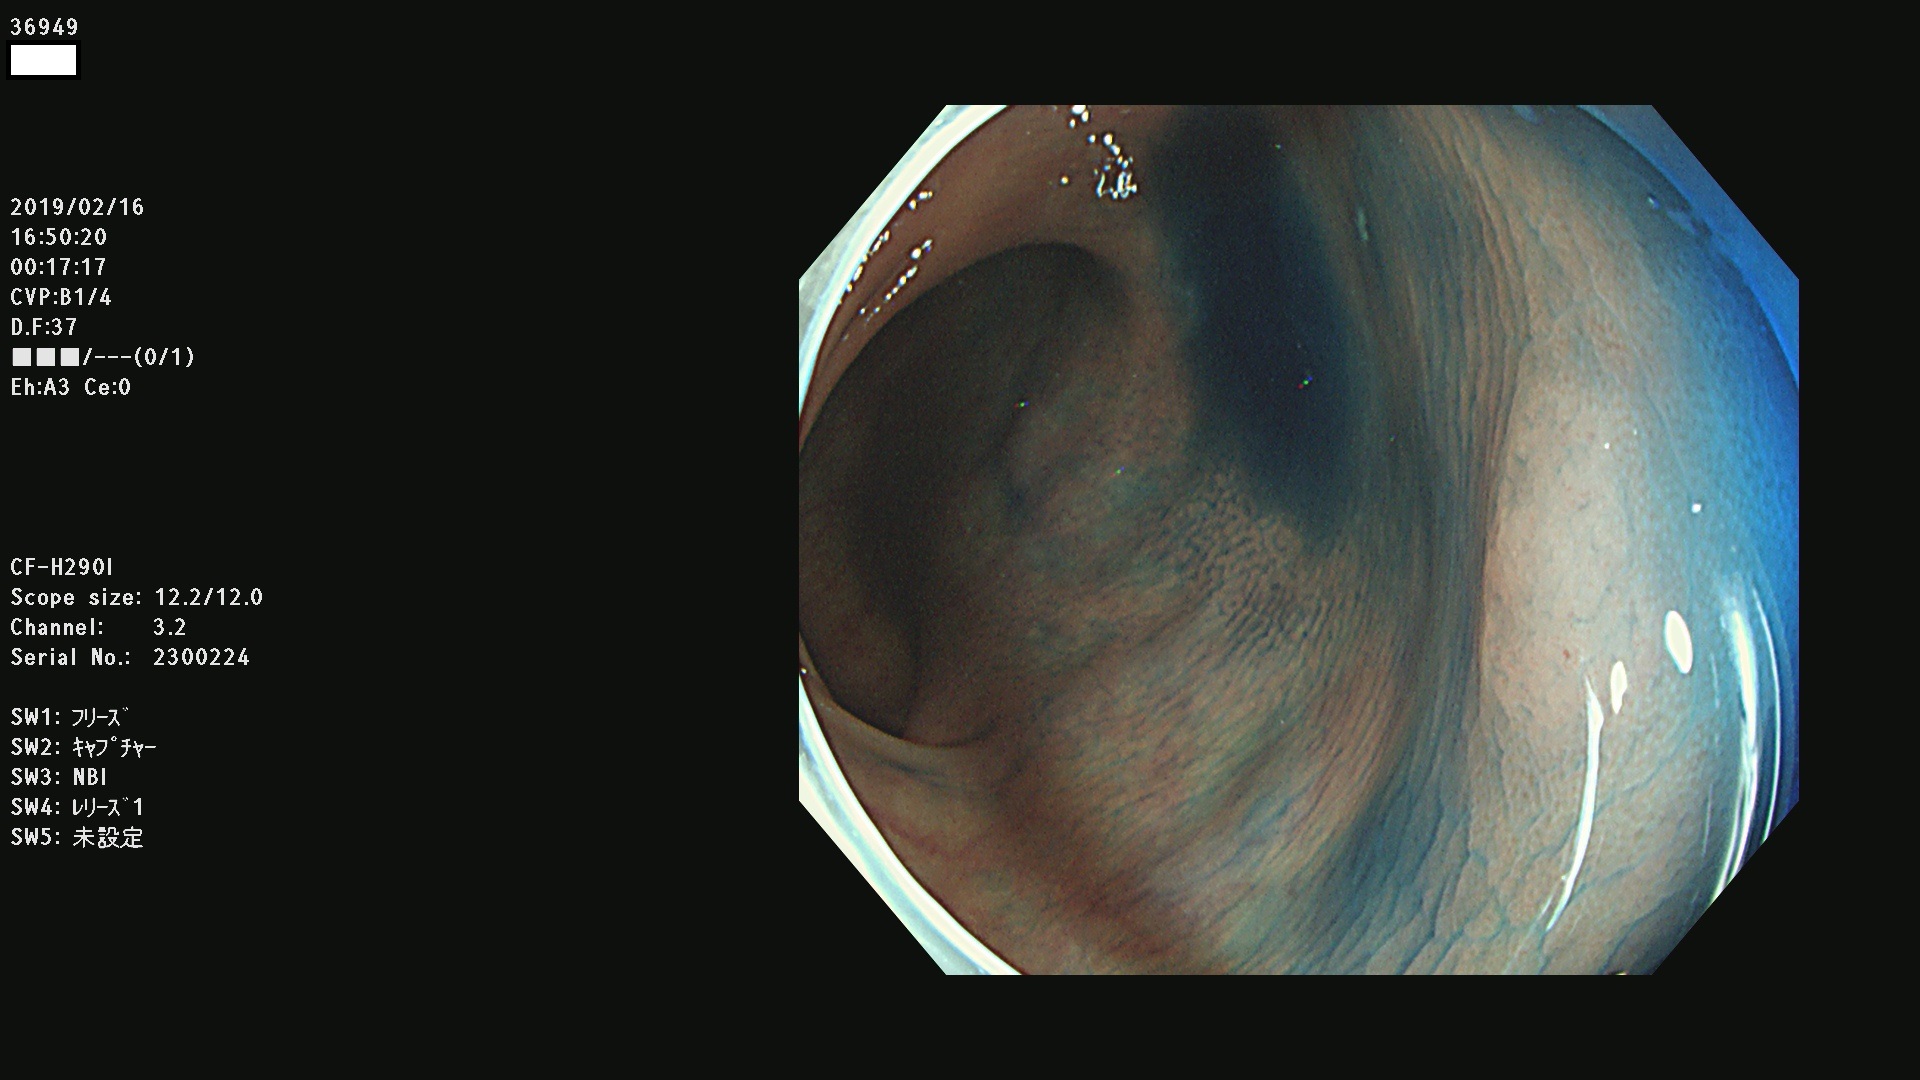

発見困難で危険性の高い平坦型病変(上記100名より抽出) ![]()